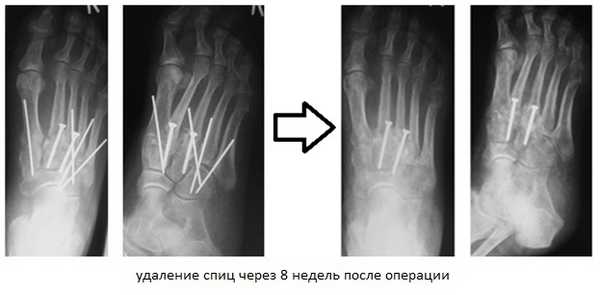

При смещении более 2 мм, нестабильности при функциональных тестах - рекомендовано открытое устранение вывиха с жёсткой фиксацией винтами или пластинами. Используются один или два продольных доступа в 1 и 2 межплюсневых промежутках. После обнажения первого предплюсне-плюсневого сустава первым этапом устраняется межклиновидная нестабильность, вторым этапом устраняется предплюсне-плюсневая нестабильность. В послеоперационном периоде сразу начинается разработка активного объёма движений. Нагрузку на стопу начинают постепенно, с тем чтобы полностью её восстановить к 6-8 неделе. Удаление спиц Киршнера производится через 6-8 недель, компрессирующих винтов через 3-6 месяцев. Возвращение к полной физической активности не ранее 9-12 месяцев после операции.

В такой ситуации остаётся один выход - операция. Необходимо освободить от рубцовых тканей весь сустав Лисфранка - а это как минимум 5 предплюсне-плюсневых суставов, вернуть плюсневые кости в нормальное положение, и зафиксировать 1-2-3 предплюсне-плюсневые суставы винтами и или пластинами, а 4-5 спицами, которые через 6 недель будут удалены.

Такая тактика диктуется тем, что в норме латеральная колонна - кубовидная кость и 4-5 плюсневые кости, являются значительно более подвижными, и эту подвижность желательно сохранить для нормальной биомеханики ходьбы.

После операции целесообразно использование внешней иммобилизации - гипсовой повязки, на срок до 6 недель. Осевую нагрузку нельзя давать до 12 недель, пока не состоится артродезирование 1-2-3 плюсневых и медиальной, срединной и латеральной клиновидных костей.

Внешний вид стопы после хирургического вмешательства, Деформация среднего отдела стопы устранена, продольный свод восстановлен. Имеющаяся деформация переднего отдела будет устраняться после заживления среднего отдела не ранее 3 месяцев от первой операции.